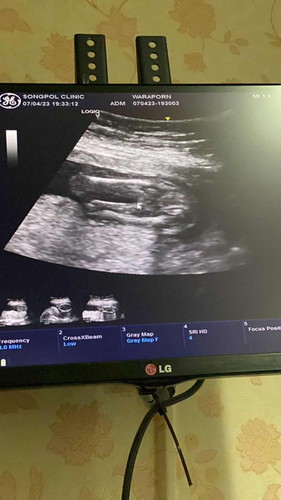

18 วีค กับการลุ้นเพศลูก

18 วีค อัลตร้าซาวด์แล้ว น้องยังหนีบๆขาไว้ หมอบอกยังไม่ชัวร์ว่าลูกชายหรือสาว แต่แนวโน้มไปทางลูกสาว แม่ท่านใดมีประสบการณ์การดูเพศลูกจากการอัลตร้าซาวด์มาแชร์หน่อยจ้า

16w4d ป้าหมอแจ้งแบบเดียวกันเลยค่ะ ว่ายังไม่เฟิร์มว่าผู้หญิงรึผู้ชาย เดือนหน้านัดอัลตราซาวด์อีกครั้งเพื่อความชัวร์ค่ะ